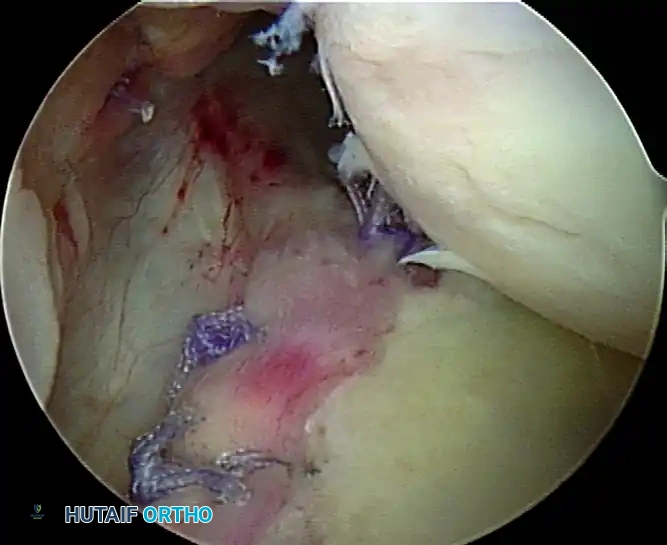

D, Knots tied re-creating soft tissue bumper.

B, Restored anterior labral bumper (arthroscopic view).

C, Restored anterior labral bumper (alternate angle).